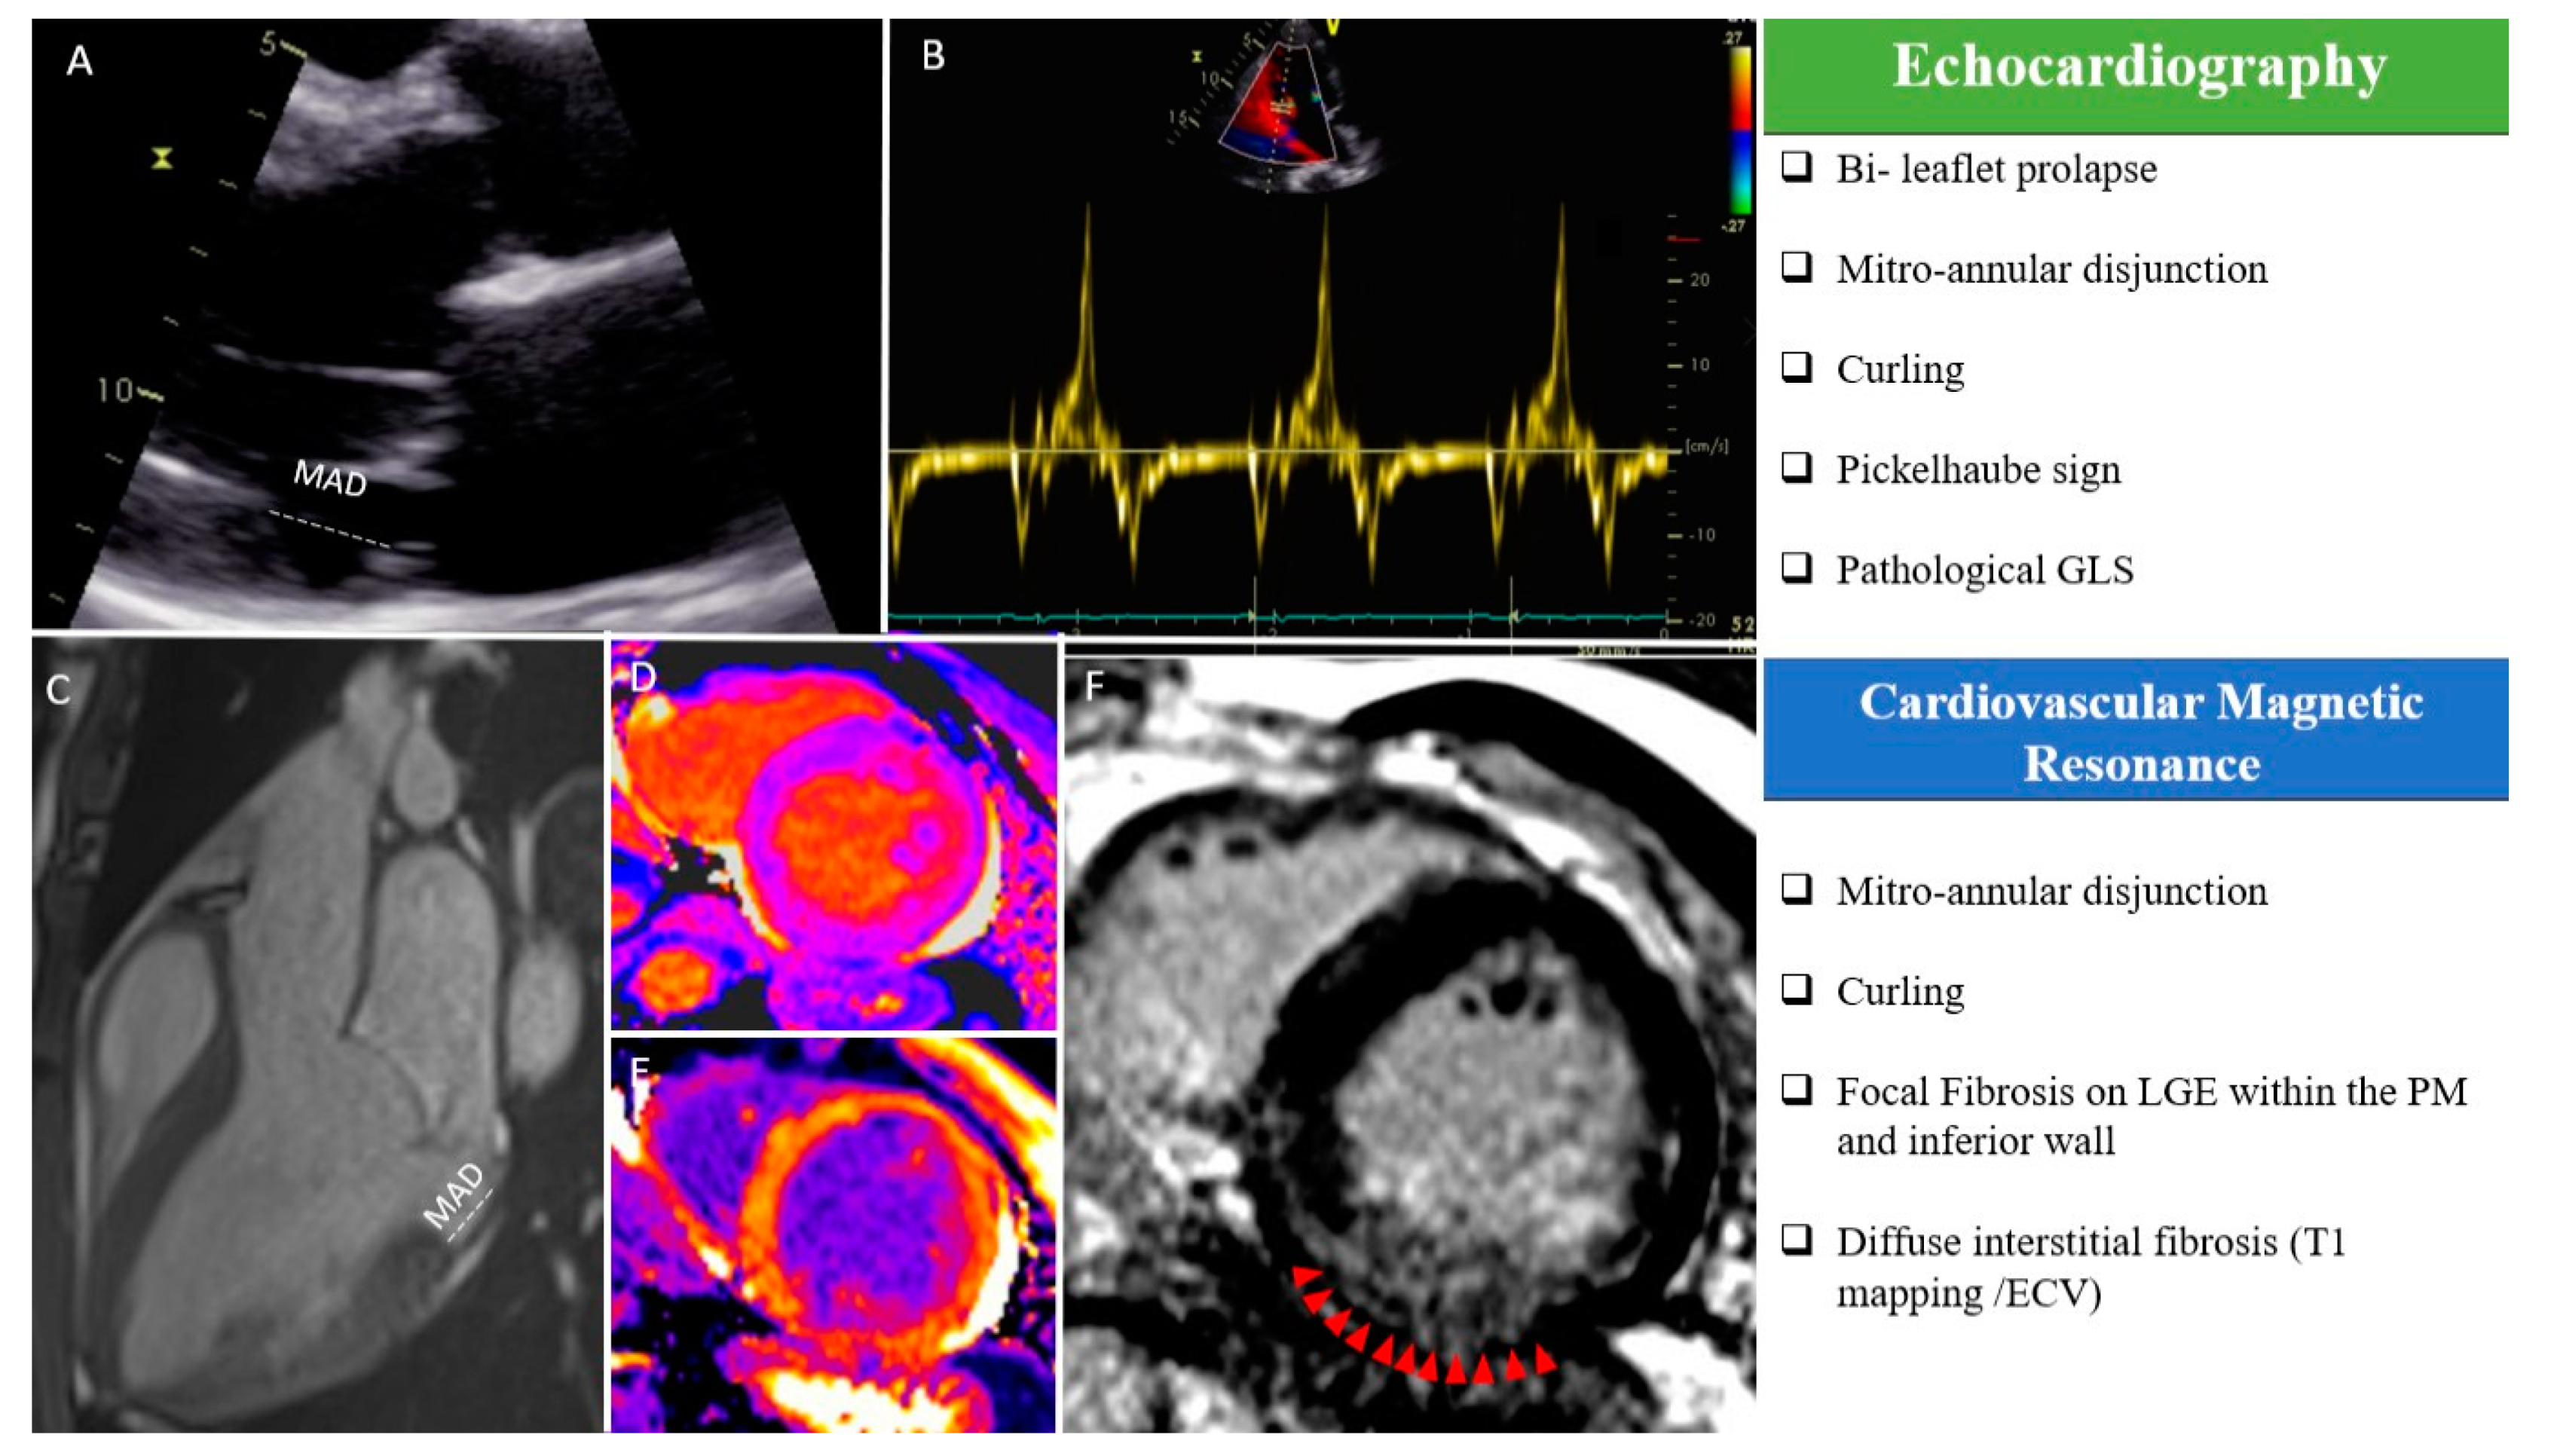

Figure 1.

“Red Flags” in echocardiography and cardiac magnetic resonance imaging (CMR): (A) MAD measured in a parasternal long-axis view (transthoracic echocardiography); (B) “Pickelhaube sign” during transthoracic echocardiography; (C) MAD measured in a steady-state free precession three-chamber view during CMR; T1 mapping native (D) and after gadolinium injection (E); macroscopic fibrosis in the inferior basal wall highlighted with red arrows in a free-breathing LGE sequence (F). ECV, extracellular volume; LGE, late gadolinium enhancement; MAD, mitro-annular disjunction; PM, papillary muscle, GLS: Global Longitudinal Strain.

TTE and transesophageal echocardiography (TEE) are the reference techniques to evaluate leaflet anatomy [12]. The “classical” definition of MVP is a single or bileaflet prolapse of at least 2 mm beyond the long-axis mitral annular plane, with or without leaflet thickening. MVP should only be diagnosed from a strict long-axis view (i.e., a parasternal or apical long-axis view), as these views cut the saddle-shaped mitral annulus at its highest point: Looking for MVP from other echocardiographic views may result in the overdiagnosis if MVP due to the complex three-dimensional shape of the mitral annulus [13]. Limitations due to a poor acoustic window may be easily overcome by TEE, and the use of three-dimensional echocardiography additionally provides a detailed evaluation of the mitral valve anatomy in “surgical view,” of the mechanism of regurgitation (including the distinction between Barlow’s disease and fibroelastic deficiency), and of the surgical reparability of the valve. While the degree of mitral regurgitation itself has not been associated with VA or SCD [7,8,14], the combination of a myxomatous valve (Barlow’s disease) with bileaflet involvement and marked leaflet redundancy during echocardiography should already raise the suspicion of aMVP and justify dedicated investigation to look for additional high-risk features associated with the MVP syndrome [7]. The tugging of the posteromedial PM in mid-systole by the myxomatous prolapsing leaflets causes the adjacent postero-basal left ventricular wall to be pulled sharply toward the apex. This brisk mid-systolic apical motion can be captured with tissue Doppler imaging of the postero-basal segment in the long-axis apical view, showing a spiked configuration of the Doppler spectrum in mid-systole, the so-called “Pickelhaube” sign (Figure 1B) [15]. It reflects the abrupt stretching of the myocardium and papillary muscles by the prolapsing valve, which may serve as a mechanical trigger of Premature Ventricular Contraction (PVC) or ventricular arrhythmia. Recent data have suggested that a spiked tissue Doppler systolic velocity ≥16 cm/s is a risk marker and should be included in the routine echocardiographic evaluation of MVP patients [15]. Regional systolic myocardial motion can also be captured by speckle-tracking echocardiography, and in a cohort of MVP patients with significant mitral regurgitation, lower global longitudinal strain values and prolonged mechanical dispersion are independently associated with the occurrence of symptomatic VA [16,17]. Pathological deformation patterns with increased pre-stretch and post-systolic contraction have also been described in the basal segments of MVP patients [18], and patients with Barlow’s disease show enhanced strain in the basal segments compared to patients with fibro-elastic deficiency or normal controls [19]. The potential importance of these features for arrhythmic risk stratification will require further investigation.

First mentioned by Bharati et al. [20], MAD refers to a displacement of the insertion point of the posterior mitral valve leaflet, which accounts for a wide separation between the left atrial wall and the left ventricle. The diagnosis of MAD is usually made in systole by measuring the distance between the posterior leaflet insertion into the left atrial wall and the base of the LV free wall [21]. This should be performed in a parasternal long axis view in echocardiography or in three-chamber view during CMR [22].

The assessment of MAD is of importance, as it has emerged as an independent risk factor for VA in several studies, probably due to its link to the mechanical stretch of the myocardium [3]. While larger degrees of MAD correlate with higher incidence of complex VA, the cut-off for MAD diagnosis is not uniformly defined. Usually the histological reference of >5 mm at the posterior leaflet level, firstly described by Hutchins et al., is considered in most echocardiographic studies (Figure 1A) [23]. However, it must be kept in mind that the circumferential extension of MAD is variable, and sometimes, the identification of MAD using TTE may be challenging [24]. The better acoustic window on TEE may overcome the disadvantage of insufficient TTE image quality, but comes at the cost of a more invasive examination [12]. On the contrary, the extent of longitudinal MAD distance located in the posterolateral wall is easily assessed by CMR [22] (Figure 1C). Essayagh et al. [8] compared TTE and CMR for the detection of MAD and found a low sensitivity (65%) but a high specificity (96%) for TTE. A recent study compared TTE, TEE, and CMR and showed only a moderate agreement between TTE and CMR, while a good agreement was found between TEE and CMR [25]. Even if not recommended in routine evaluation, cardiac computed tomography also allows to measure the length of MAD [26].

Notably, an unusual systolic motion of the posterior mitral ring and the adjacent myocardium may also be found in patients with aMVP (“Curling”) [3,10]. This specific movement has been linked in several series with the presence of MAD and it contributes to the paradoxical increase in the mitral annulus diameter during systole and the relative hypertrophy of the hypermobile postero-basal segments [7]. It may be associated with the development of LV fibrosis, accounting for the excessive mobility of the MV apparatus and systolic stretch of the myocardium closely linked to the valve. For the moment, only a visual non-quantitative assessment is typically performed, while no specific cut-off has been identified (Video S1: Curling motion during transthoracic echocardiography; Video S2: Curling motion during CMR; Supplementary Materials).

The presence of fibrosis at the PM and inferior LV wall level is another key feature of aMVP and has been proposed as an independent risk factor for VA and SCD [27]. CMR is the only imaging technique that allows for a detailed evaluation of myocardial tissue characteristics, but until now, it has not been routinely used in patients with MVP.

Basso et al. [27] demonstrated in 2015, by histopathologic analyses in young SCD victims with MVP and trivial mitral regurgitation, a high prevalence of myocardial fibrosis in the LV infero-basal wall and in the PMs. These findings were confirmed in vivo in a subpopulation of MVP patients with complex ventricular arrhythmias, in whom CMR showed a late gadolinium enhancement (LGE) distribution similar to the histopathologic findings observed in SCD victims. These myocardial fibrotic alterations have been confirmed in other studies [6,7,8,14,28], and are probably linked to the mechanical stretch acting upon the valve and the neighboring LV myocardium and could represent the arrhythmic substrate in patients with MVP. However, identification of LGE at the PM level and neighboring LV walls may be challenging even for CMR experts, and additional non-standard views may be needed to best visualize fibrotic regions in the myocardium (Figure 1F). Undoubtedly, this evidence supports the need for a CMR examination with LGE acquisitions in all patients with suspected aMVP.

Pradella et al. [33] and Bui H et al. [34] found globally higher native and lower post-contrast T1 myocardial values, suggesting the presence of interstitial fibrosis, but no association with complex VA was found (Figure 1D,F). However, their studies suffered from various limitations, in particular, the lack of a control group (patients with mitral insufficiency but without MVP) and the absence of a multivariate analysis considering the presence of other high-risk features. Moreover, Guglielmo et al. highlighted that patients with MVP have higher native T1 times compared to healthy controls, particularly in the basal and mid-LV inferolateral walls; higher T1 values were not correlated with MR severity, indicating that diffuse fibrosis may not only be a consequence of volume overload [35].